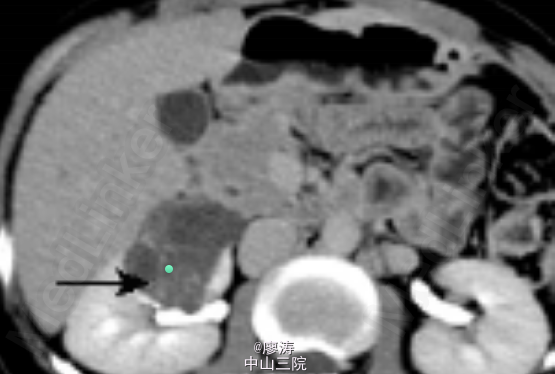

主诉:肾移植术后8年,发现血尿3天 病史:患者男,45岁,8年前因尿毒症在我院行异体肾移植术,手术过程顺利,术后恢复良好,服用FK506+MMF+强的松免疫抑制维持治疗,肌酐约110umol/L。2015-5-12开始出现肉眼血尿,无尿频尿急尿道,无尿路刺激症状,于15/5来我院就诊,门诊以“异体肾移植状态,血尿查因”收入院。

入院后查血肌酐为158umol/L,移植肾功能良好。腹部CT提示右肾巨大占位性病变,且分隔,考虑右肾肾癌。

诊断:右肾占位性病变,考虑右肾肾癌 处理:检查提示肾癌可能性大,跟患者和患者家属讨论后决定手术治疗,于是在入院后第3天在我院行右侧肾癌根治术,术后取活检确诊为肾癌,术后结合化疗。